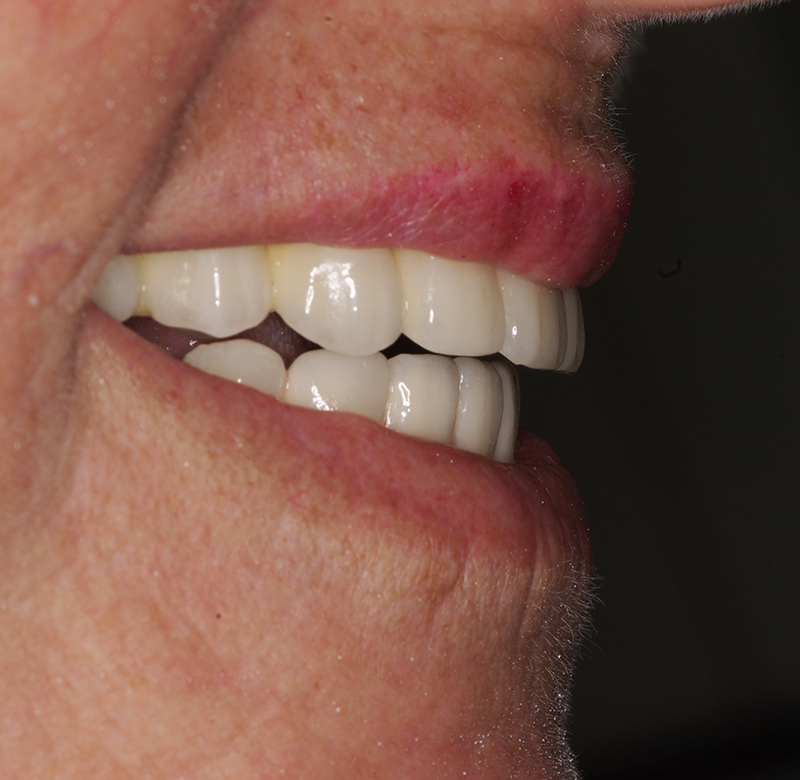

Carga Imediata: Restauração Imediata do Sorriso com Tecnologia de Ponta

A técnica de Carga Imediata tem revolucionado o campo da odontologia, permitindo aos pacientes recuperar funcionalidade e estética em tempo recorde. Se você busca um tratamento eficiente e moderno para restabelecer seu sorriso, este procedimento pode ser ideal para você.

- Recuperação rápida: O paciente sai do consultório com um sorriso renovado em questão de dias.

- Conforto e Estética: A prótese provisória é funcional e visualmente semelhante aos dentes naturais.

- Melhora da autoestima: O impacto positivo de um sorriso completo é imediato, melhorando a qualidade de vida.